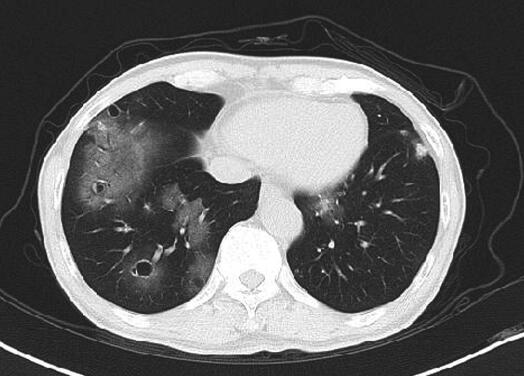

入院时生命体征平稳,体型偏瘦,余未见明显阳性体征。入院后积极完善血尿便常规、风湿免疫相关化验,如ANCA系列、补体等及痰培养、痰涂片找结核菌、痰涂片找真菌等,同时经验性给予头孢西丁联合左氧氟沙星抗感染治疗5天,患者咯血量无明显变化。期间化验回报:血细胞分析示血象正常,尿常规示潜血弱阳性,镜检红细胞数正常,ANCA、狼疮系列、补体系列均大致正常,两次痰涂片找真菌回报可见真菌孢子及菌丝,两次痰培养回报为白念珠菌,11月3日复查胸部CT(图2)示空洞病灶较前增多,空腔增大,遂调整治疗方案为头孢哌酮舒巴坦、替硝唑及卡泊芬净治疗2周,患者咯血量较前增多,约20~30ml/d,11月16日复查胸部CT(图3),双肺空腔病灶较前继续进展,11月18日行气管镜检查示左、右主支气管及其所属所见各分支支气管黏膜光滑,轻度充血水肿,各管腔内可见血性分泌物,充分吸引后可见右下基底各段支气管及左舌叶支气管管腔黏膜不断有新鲜血液溢出,以右下后基底段为主,管腔远端未见血液溢出,支气管刷检及灌洗液找结核菌均为阴性。结合患者病史、症状、体征及胸部影像学、气管镜下特点,双肺空洞病灶性质仍不明确,考虑到患者支气管管腔溢血较多,经皮肺穿刺活检出血风险大,建议其可考虑胸腔镜肺活检术,协助明确双肺病灶性质,患者本人表示拒绝。患者给予经验性抗细菌、抗真菌治疗后,双肺病灶仍有进展,提示治疗无效,停用所有抗生素,给予口服某中成药止血胶囊及更换义齿后,咯血次数逐渐减少至2~3口/日,为痰中带暗红色血块,并建议其于上级医院进一步诊治。11月26日就诊于北京某三甲医院,12月1日行胸部增强CT(图4)示双肺多发囊泡影,黏液腺癌?血管肉瘤?肺吸虫?并转入胸外科行胸腔镜下肺活检术,术中快速冰冻病理示恶性肿瘤。12月18日病理回报为肺低分化恶性肿瘤,倾向低分化癌,同时送检病理切片于外院会诊。12月26日两家医院病理会诊结果回报为低分化鳞癌。1月4日行PET-CT回报双肺内多发薄壁空洞,周围伴磨玻璃影,空洞壁代谢异常增高,右肺近肺门代谢增高结节,均考虑为恶性病变,余未见明显异常。

图2 2014年11月3日胸部CT

双肺空洞病灶较入院时略有进展